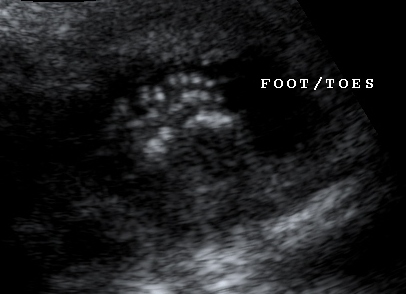

5ヶ月(16週4日) 5ヶ月(16週4日)

両足の裏。小っちゃいけど ママとパパに向かって「ニコッ」

指はちゃんと5本づつあるよ。 顔の輪郭や耳の形がパパにそっくり!

どうか健康で五体満足に生まれてきてね。 実はこの日、性別が判明。男の子を欲しがっ